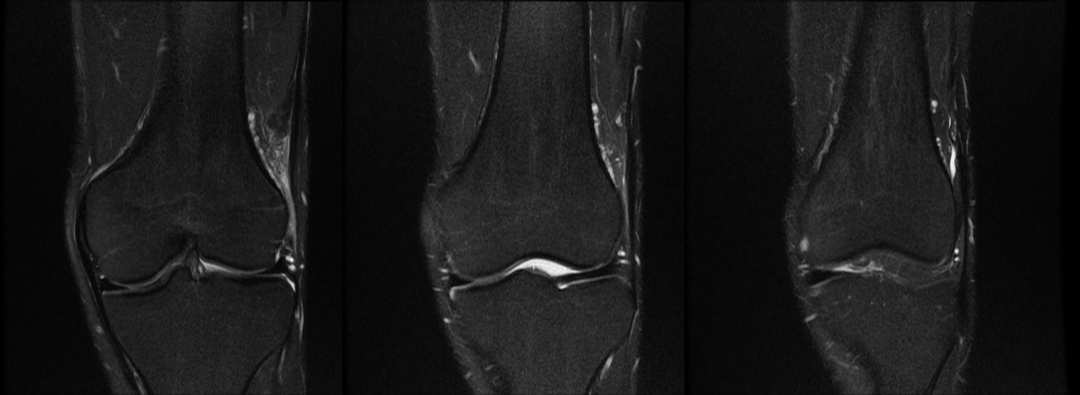

主诉:右膝关节外侧反复疼痛不适半年余,近一个星期疼痛加重。现病史:患者右膝关节外侧间歇性疼痛不适半年余,近一个星期疼痛加重,屈膝时明显,门诊行膝关节 X 线片检查,未见明显异常。患者否认手术史/外伤史。为进一步明确情况,我们建议患者行膝关节磁共振检查;图像如下:T1

T2 压脂

冠状位

大家是否发现什么异常?该患者是膝外侧疼痛不适的症状,我们重点观察了外侧半月板及外侧副韧带,但是我们发现是正常的;

但是我们发现有一个地方信号不对;

大家发现了没有?那这是什么呢?

那么我们刚刚看到信号增高的就是髂胫束,排除了半月板和外侧副韧带的问题,那么膝关节外侧疼痛是不是这个原因导致的呢?

1 T2WI PD 序列上可以显示靠近股骨外侧髁与髂胫束之间的信号增高,边界不清,外侧滑膜增厚;

2 髂胫束靠近股骨外侧髁水平出现增厚改变,部分严重患者可以出现连续性中断;3 髂胫束表面或深部信号明显增高;4 可伴股骨外侧髁反应性骨髓水肿